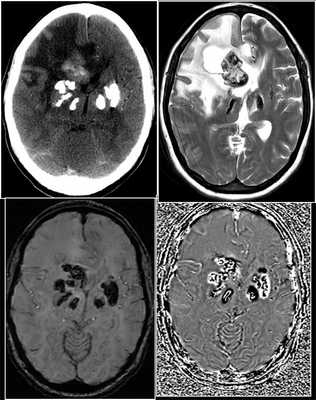

- Церебральные микрокровоизлияния, связанные с заболеваниями сердца

Различные кардиологические состояния могут выступать в качестве основного источника эмболии, которая может проявляться в виде ТИА, ишемии или кровотечения в головном мозге. Частые состояния, которые могут привести к микрокровоизлияниям, включают инфекционный эндокардит, предсердную миксому и протезированные клапаны. Церебральные микрокровоизлияния не являются редкостью у пациентов с приобретенным инфекционным эндокардитом (57% в группе с эндокардитом, по сравнению с лишь 15% в контрольной группе) ( рис. 7 ). Кровоизлияния, как правило, происходили в корковых бороздах, что можно объяснить тем фактом, что некоторые из поражений, могли быть грибковыми аневризмами.